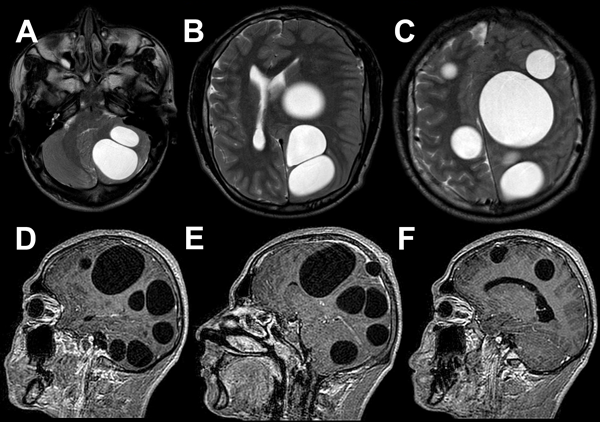

Para mejor valoración de las lesiones cerebrales, se solicitó resonancia magnética cerebral con contraste que informó: a nivel supratentorial, en secuencia T2 y FLAIR, múltiples imágenes quísticas de gran tamaño, la mayor de ellas a nivel frontoparietal izquierdo de aproximadamente 100 ml con discreta desviación de línea media, gran efecto de masa y colapso ventricular. Posterior a esta última se observaron otras dos lesiones de voluminoso tamaño; a nivel infratentorial se evidenciaron dos lesiones de similares características con importante efecto de masa (Figura 2).

Figura 2. A-C) RM T2 axial preoperatoria, se evidencian múltiples quistes hiperintensos en hemisferio cerebeloso izquierdo y ambos hemisferios cerebrales. D-F) RM T1 con contraste sagital preoperatorias, se observan las mismas lesiones que en secuencia anterior sin realce de contraste.

En el control postoperatorio a los 6 meses, todavía en tratamiento antiparasitario, el paciente no presentó deterioro clínico y la resonancia magnética de control mostró la disminución del tamaño de una de las lesiones preexistentes en fosa posterior sin modificaciones en las restantes (Figura 5). Ante estos hallazgos, se propuso la reintervención de las lesiones remanentes, pero el paciente rechazó el procedimiento.

Figura 5. A) RM T2 axial postoperatoria (6 meses). Se evidencia disminución del tamaño quístico en hemisferio cerebeloso. B-C) RM T2 axial. Se muestran cambios postoperatorios y quistes remanentes de igual tamaño. D-F) RM T1 con contraste sagital postoperatorias (6 meses). Se visualiza realce con contraste en lodge quirúrgica y remanentes quísticos de similares características.